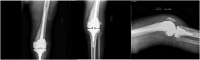

A 74-year-old male with a prior left total knee arthroplasty presented with deformity, loosening, pain, and stiffness associated with multiple raised, erythematous, cutaneous nodules about the anterior knee. Workup was concerning for infection, but the skin nodules were atypical. The patient was sent for biopsy which revealed cutaneous diffuse large B-cell lymphoma. The revision surgery was delayed, and the patient underwent chemotherapy/radiation with complete resolution of his lymphoma. He then underwent a successful aseptic revision total knee arthroplasty. Proper identification and treatment of rare cutaneous skin lesions about a prior surgical site can limit morbidity and result in more desirable outcomes.